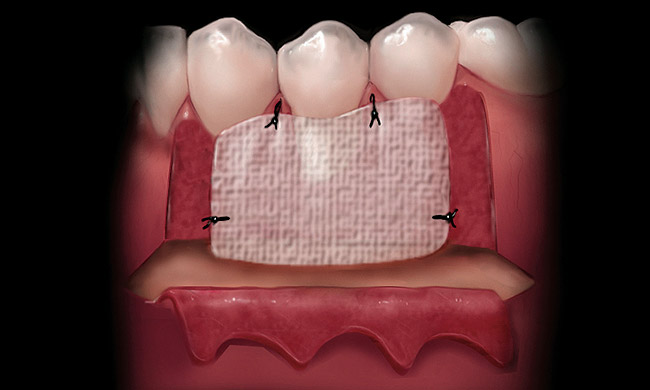

If acelluar connective tissue is used, place the rehydrated piece of acellular dermal allograft on the site to allow blood to contact the material, making sure to touch both sides to the recipient bed. The side that retains the coloration from the blood (red side) should be placed over the recipient bed facing away from the roots. This technique places the “white” side (basement membrane side) toward the root surface to be grafted. The connective tissue is placed over the root exposure and secured with 5-0 polyglycolic acid (PGA) sutures (Figure 8).12 The apical boarder of the graft is not sutured so that apical tension is not placed upon the graft during function as healing occurs.13

Figure 8  The connective tissue is sutured over the recipient bed.

Figure 8